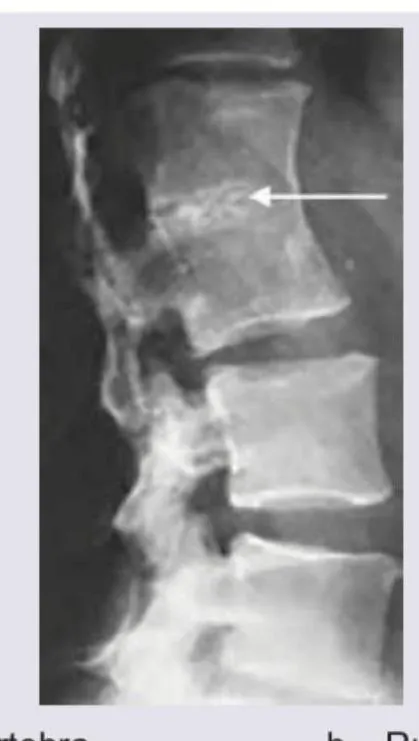

| Fracture | Significant trauma, age >50 + minor trauma, prolonged corticosteroid use, osteoporosis | XR spine ± MRI |

Age & Trauma Screen:

- Age >50 + new-onset back pain = consider malignancy/fracture

- Significant trauma at any age = XR spine

- Minor trauma + age >50/osteoporosis = XR spine